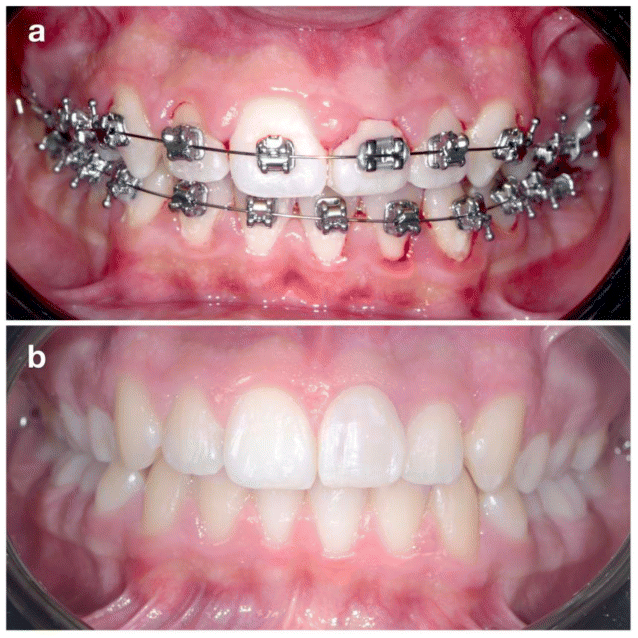

A 13-year-old male patient presented with his parents to evaluate the possibility of orthodontic treatment due to anterior crowding. Clinically confirmed anterior crowding and revealed a buccal fistula in the regions of teeth 2.1 and 2.2 (Figure 1a). The maxillary left central incisor (2.1) had sustained trauma at the age of 8, resulting in a complicated crown fracture with pulp exposure, treated at that time by apexification and coronal restoration (Figure).

Postoperative management included systemic antibiotics, analgesics, and chlorhexidine rinses. At 10 days, the gingiva appeared healthy with no periodontal probing. At 4 weeks, composite resin was applied to reshape the transplanted premolar into an incisor morphology (Figure 6a). Orthodontic treatment resumed at 8 weeks. After 12 months, CBCT confirmed complete healing without root resorption or periapical pathology (Figure 7). The radiographic images reveal complete resolution of the initial osteolytic lesion and full regeneration of the alveolar socket surrounding the root of the transplanted tooth. Moreover, the vestibular bone wall has entirely reconstituted, closely following the anatomical contour of the tooth root. The contralateral premolar (1.5) was later extracted as part of the orthodontic plan completed in 10 months. Definitive composite restoration was placed after completion of orthodontic treatment (Figure 6b).